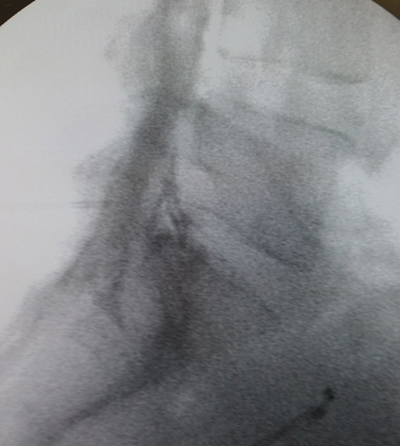

Figura 1